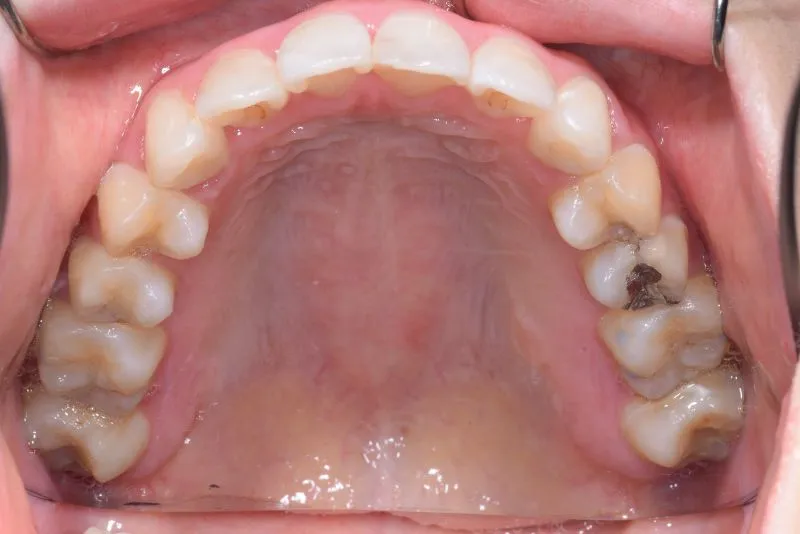

• 初診時

初診時

初診時年齢 19~29歳 (女性) 主訴 上下がガタガタ・出っ歯

診断名 叢生・上下顎前突 装置名

上下の歯並びがガタガタで口元が出ています。

元々小学生の時にマルチブラケット装置を上下につけ、矯正治療を受けていました。

何年か経過後、ガタガタと口元が気になると受診されました。

後戻りの原因は、リテーナーの装着時間不足、頬杖や、口呼吸などが考えられます。